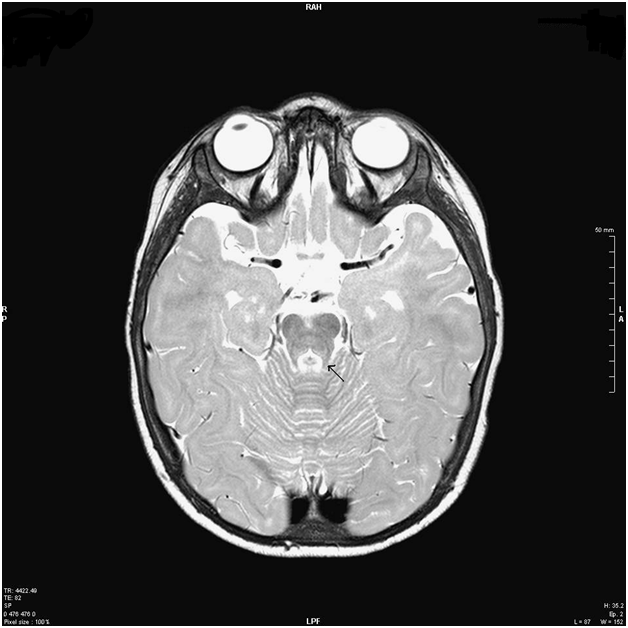

A dysmorphism of the corpum callosum and subependimal noduli near the trigonus and in the posterior segment of the right temporal lobe was shown. The MRI results suggested a final diagnosis of pontine cap dysplasia (PTCD) and periventricular nodular heterotropia (PNH) (Figure 2&3). To exclude that the behavioral responses depended from saccular hearing, further the cervical-vestibular evoked myogenic potentials (cVEMP) were measured to assess the presence of saccular and vestibular nerve responses were present but with low amplitude on the left side, while they were absent on the right side.

Figure 3 Axial T2-weighted MRI image showing molar-tooth-like sign.